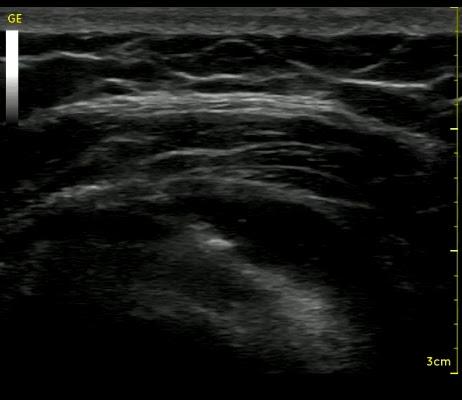

Έγχυση PRP σε μερική ρήξη υπερακανθίου

Έγχυση πλάσματος πλούσιου σε αιμοπετάλια (Platelet Rich Plasma, PRP) σε χρόνια τενοντίτιδα του υπερακανθίου